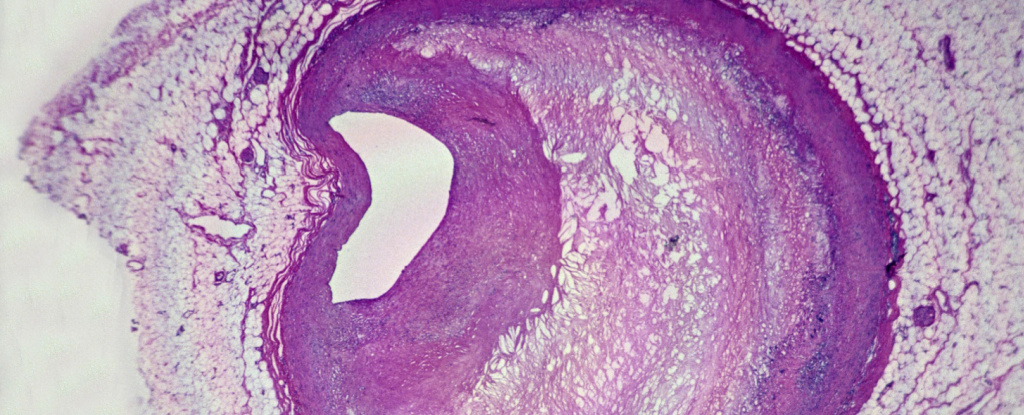

Мікропластики також були видимі під потужними мікроскопами: дослідники спостерігали пластикові фрагменти з зубчастими краями всередині клітин імунної системи, званих макрофагами, і в жирових бляшках. Під час вивчення тканинних зразків команда також знайшла підвищені рівні запальних маркерів у пацієнтів з мікропластиками в їх бляшках.